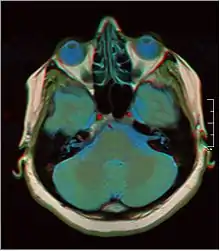

False color MRI by applying red to T1, green to PD and blue to T2.

A number of different imaging modalities or sequences can be used with imaging the nervous system:

• T1-weighted (T1W) images: Cerebrospinal fluid is dark. T1-weighted images are useful for visualizing normal anatomy.

• T2-weighted (T2W) images: CSF is light, but fat (and thus white matter) is darker than with T1. T2-weighted images are useful for visualizing pathology.[26]

• Diffusion-weighted images (DWI): DWI uses the diffusion of water molecules to generate contrast in MR images.

• Proton density (PD) images: CSF has a relatively high level of protons, making CSF appear bright. Gray matter is brighter than white matter.[27]